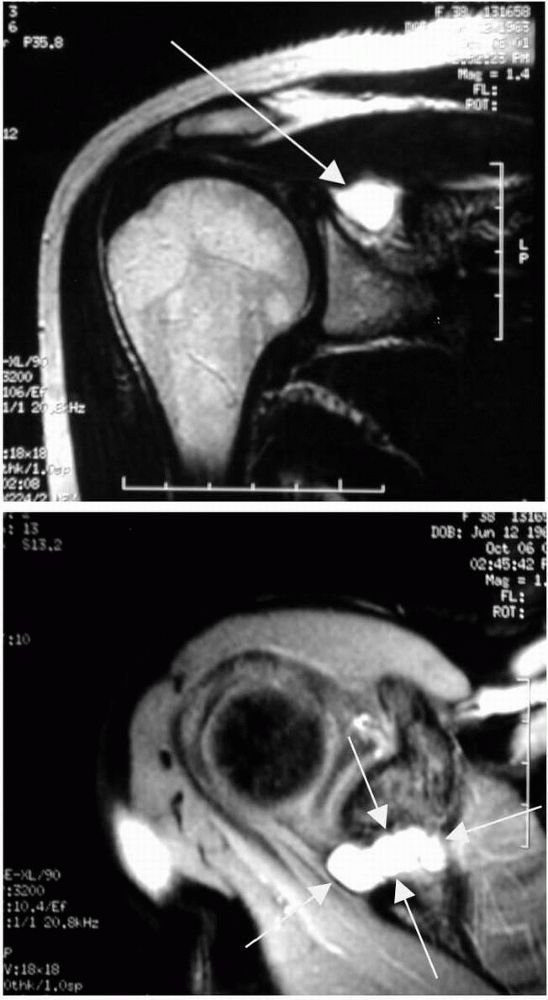

Signal intensity on MRI depends on water and fat variations and

therefore can reveal osteonecrosis prior to radiograph changes (Figure 12-12).

![]() |

|

FIGURE 12-11. Avascular necrosis of the humeral head with collapse of the subchondral bone.

FIGURE 12-12. Coronal MRI image of avascular necrosis of the humeral head (depicted by white arrows).